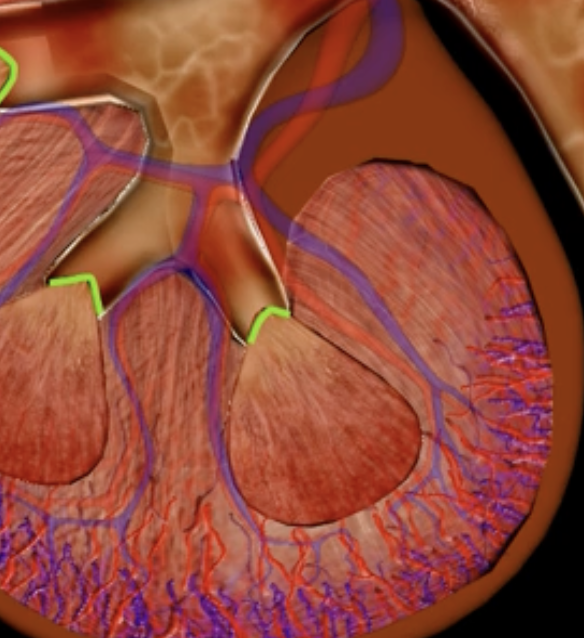

minor calyx

teal

major calyces

blue

renal pelvis

minor and major calyces

renal medulla

renal pyramids

renal lobe